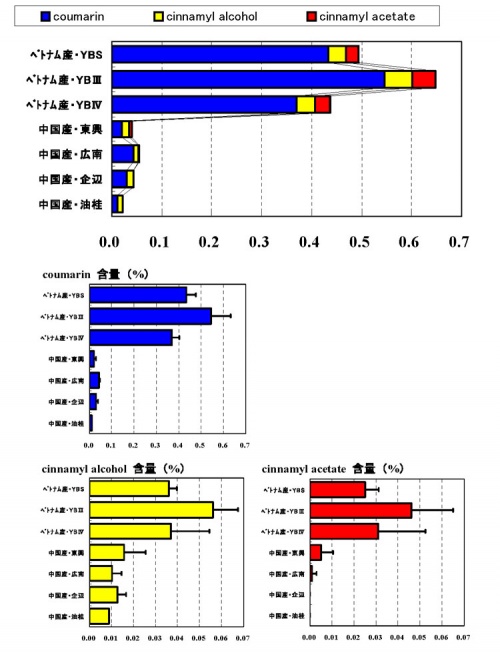

理化学的品質評価

| 産地&規格 | 検体数 | 灰分 6.0%以下 |

乾燥減量 15.5%以下 |

希エタノール エキス含量 |

精油含量 0.5mL/50.0g以上 |

|---|---|---|---|---|---|

| ベトナムALL | 138 | 4.2 ±0.7 | 14.3 ±1.2 | 12.6 ±2.2 | 2.41 ±0.61 mL |

| YBS | 7 | 4.3 ±0.8 | 15.3 ±1.2 | 12.0 ±1.9 | 3.23 ±0.91 mL |

| YBⅠ | 5 | 4.0 ±1.2 | 14.1 ±0.5 | 13.1 ±3.0 | 3.04 ±0.73 mL |

| YBⅢ | 34 | 4.5 ±0.5 | 14.5 ±0.9 | 12.2 ±2.2 | 2.53 ±0.43 mL |

| YBⅣ | 30 | 4.3 ±0.6 | 14.2 ±1.3 | 12.9 ±1.8 | 2.26 ±0.50 mL |

| YBⅤ | 46 | 3.9 ±0.5 | 14.2 ±1.3 | 12.6 ±2.0 | 2.28 ±0.40 mL |

| 中国ALL | 179 | 2.9 ±0.7 | 13.4 ±1.2 | 11.7 ±3.1 | 1.26 ±0.40 mL |

| 企辺 | 14 | 3.4 ±0.8 | 13.8 ±1.1 | 10.4 ±2.5 | 1.54 ±0.44 mL |

| 油桂 | 24 | 3.4 ±0.5 | 13.5 ±1.2 | 10.6 ±3.8 | 1.58 ±0.34 mL |

| 東興 | 26 | 3.4 ±0.6 | 13.4 ±1.2 | 10.4 ±3.2 | 1.37 ±0.34 mL |

| 西江 | 40 | 2.6 ±0.5 | 13.3 ±1.3 | 12.0 ±2.4 | 1.08 ±0.25 mL |

| 広南 | 45 | 2.7 ±0.5 | 13.2 ±1.3 | 13.1 ±2.6 | 1.17 ±0.36 mL |

- ベトナムALLと中国ALLの比較

- 灰分

- ベトナムALL > 中国ALL ( p < 0.05 )

- 希エタノールエキス含量

- ベトナムALL > 中国ALL ( p < 0.05 )

- 精油含量

- ベトナムALL > 中国ALL ( p < 0.05 )

- ベトナム産の規格(等級)による比較

- 灰分

- YBⅢ > YBⅤ ( p < 0.05 ). その他は有意差無し.

- 希エタノールエキス含量

- いずれも有意差無し.

- 精油含量

- YBS, YBⅠ > YBⅢ > YBⅤ,YBⅣ ( p < 0.05 )

- 中国産の規格による比較

- 灰分

- 企辺, 東興, 油桂 > 広南, 西江 ( p < 0.05 )

- 希エタノールエキス含量

- 広南 > 西江 > 油桂, 東興, 企辺 ( p < 0.05 )

- 精油含量

- 油桂, 企辺, 東興 > 広南, 西江 ( p < 0.05 )

- 油桂 > 東興 ( p < 0.05 )

| 産地&規格 | 検体数 | cinnamic acid | cinnamaldehyde |

|---|---|---|---|

| ベトナムALL | 198 | 0.062 ±0.021 | 4.63 ±1.23 |

| YBS | 15 | 0.070 ±0.021 | 5.61 ±1.24 |

| YBⅠ | 8 | 0.083 ±0.026 | 5.92 ±1.59 |

| YBⅢ | 65 | 0.060 ±0.023 | 4.75 ±1.18 |

| YBⅣ | 43 | 0.052 ±0.015 | 4.06 ±1.06 |

| YBⅤ | 63 | 0.063 ±0.016 | 4.48 ±1.13 |

| 中国ALL | 191 | 0.063 ±0.029 | 2.83 ±0.74 |

| 企辺 | 15 | 0.049 ±0.017 | 3.21 ±0.65 |

| 油桂 | 16 | 0.053 ±0.029 | 3.17 ±0.91 |

| 東興 | 39 | 0.075 ±0.035 | 3.15 ±0.65 |

| 西江 | 42 | 0.048 ±0.021 | 2.35 ±0.49 |

| 広南 | 42 | 0.063 ±0.022 | 2.65 ±0.63 |

- ベトナムALLと中国ALLの比較

- cinnamic acid

- ベトナムALLと中国ALLで有意差無し.

- cinnamaldehyde

- ベトナムALL > 中国ALL ( p < 0.05 )

- ベトナム産の規格(等級)による比較

- cinnamic acid

- YBⅠ, YBS > YBⅤ, YBⅢ > YBⅣ ( p < 0.05 )

- cinnamaldehyde

- YBⅠ, YBS > YBⅢ, YBⅤ, YBⅣ ( p < 0.05 )

- 中国産の規格による比較

- cinnamic acid

- 東興 > 油桂, 企辺, 西江 ( p < 0.05 ).

- 広南 > 企辺, 西江 ( p < 0.05 )

- cinnamaldehyde

- 企辺, 油桂, 東興 > 広南 > 西江 ( p < 0.05 )